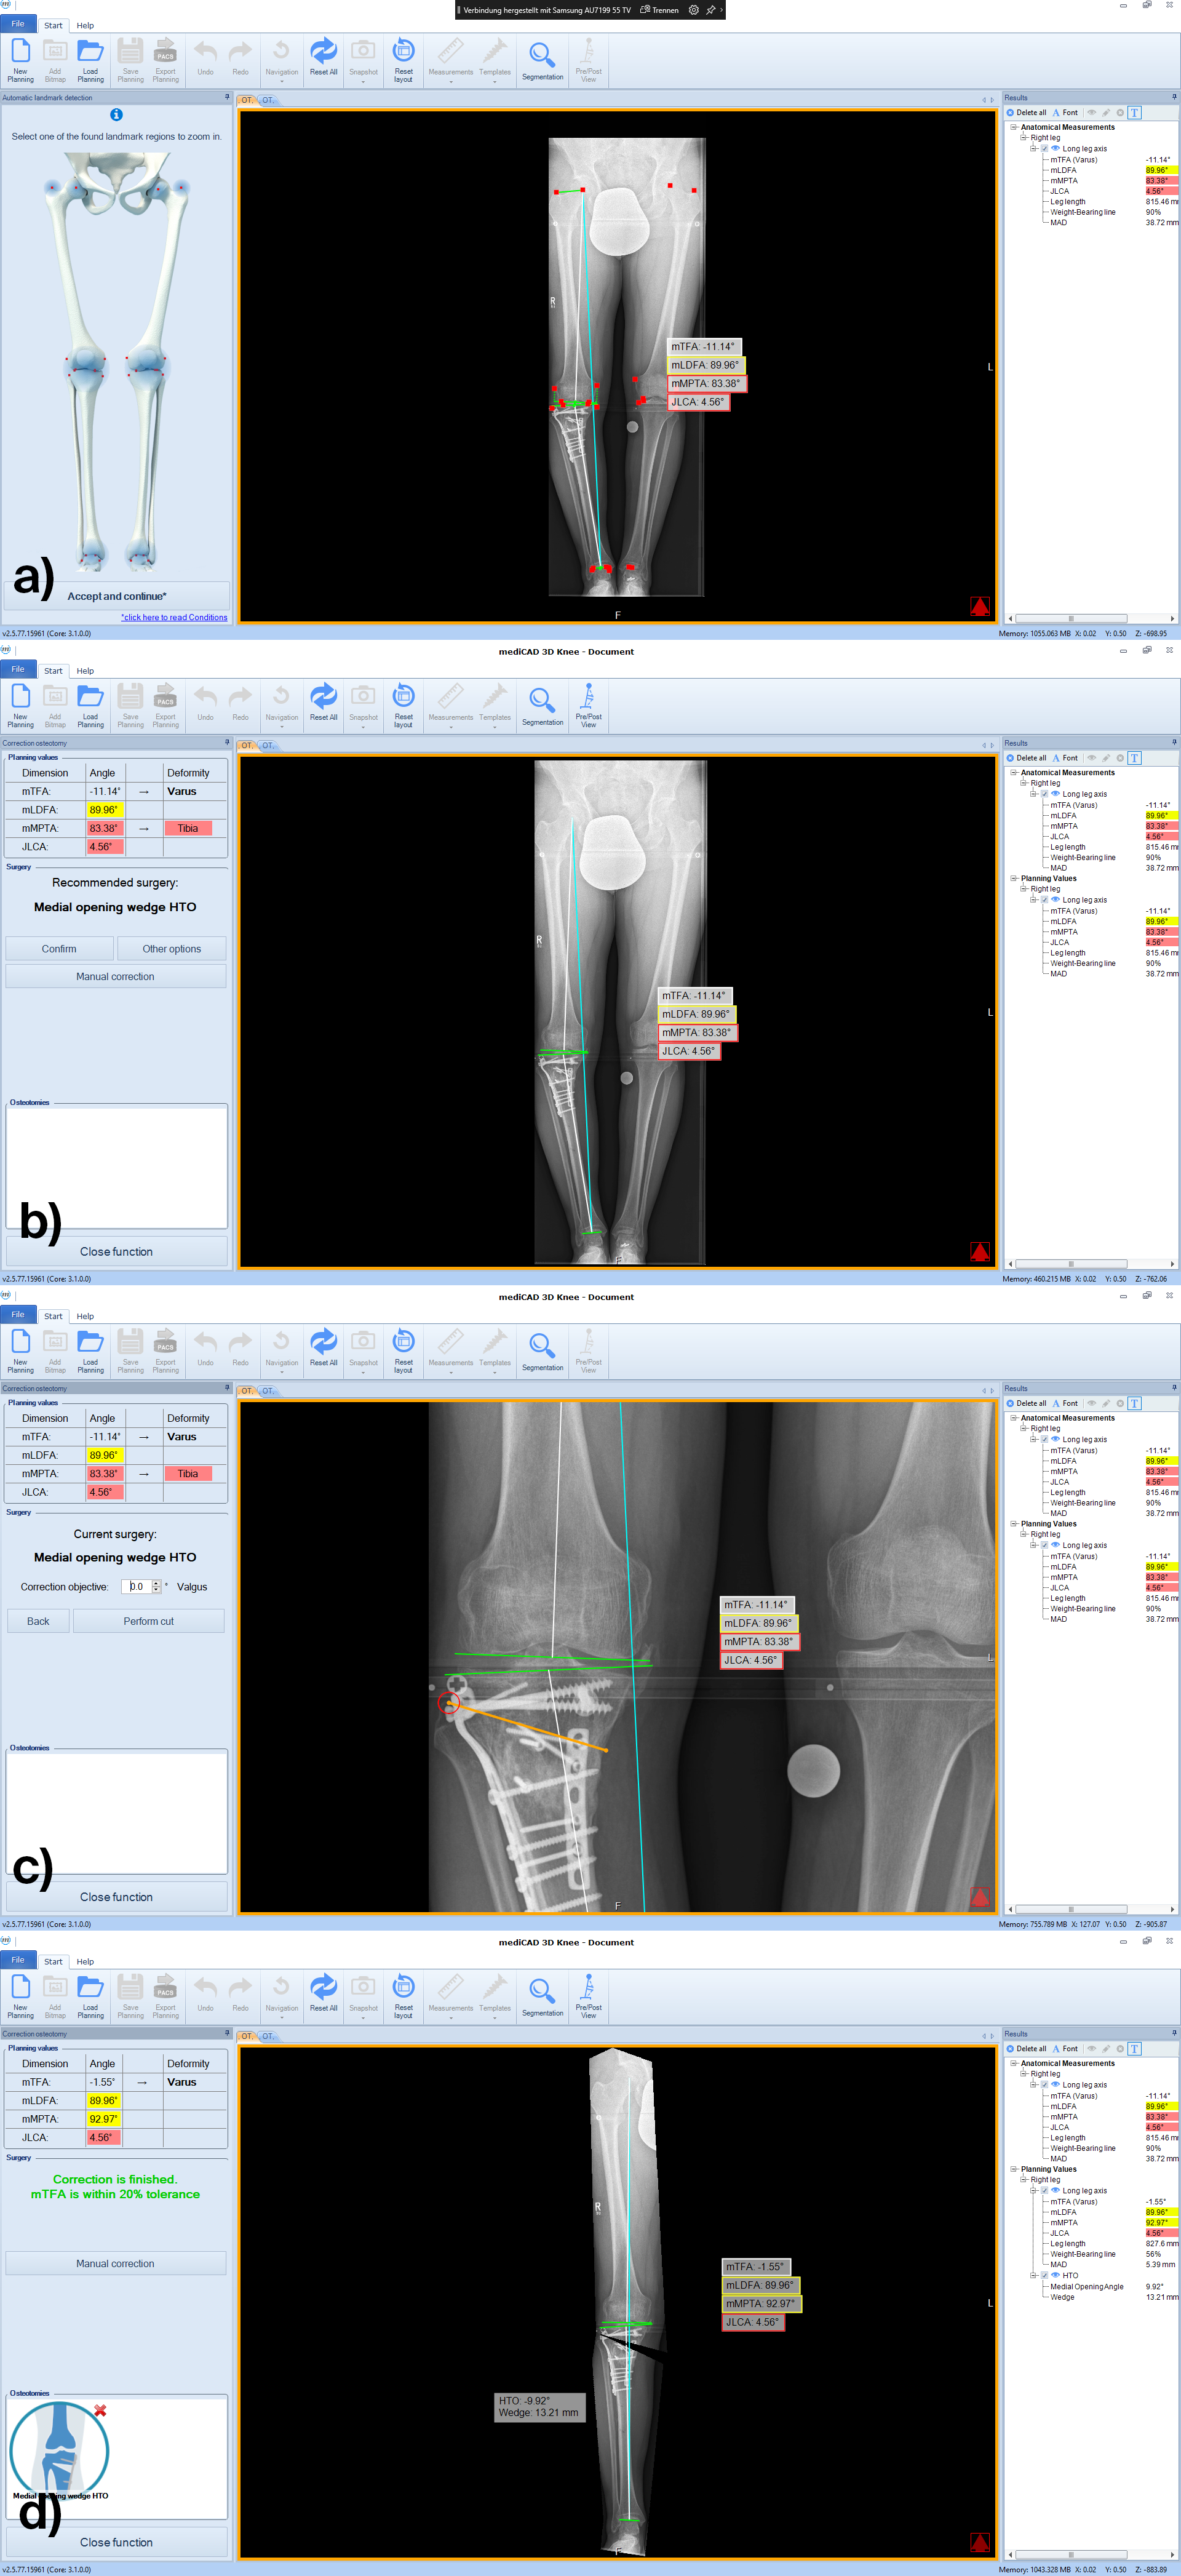

Following the deformity analysis, the software automatically recommends a surgical procedure, eg, medial opening wedge high tibia osteotomy, depending on the type of deformity (Fig 2). The user can follow the proposed procedure or choose individual options.

Once the procedure is selected, the software automatically places the cutting line and hinge point for the chosen osteotomy adapted to the individual anatomical condition (Fig 3).

Next, deformity correction is visualized to the preferred new alignment. If a monofocal correction results in pathological joint angles, the implemented algorithm recommends double-level osteotomy and balance the two osteotomies between multiple constraints and normal values such as wedge heights, mechanical medial proximal tibial angle (mMPTA), mechanical lateral distal femoral angle (mLDFA), mechanical tibiofemoral angle (mTFA); (Fig 4).

A 52-year-old man with a posttraumatic deformity 2 years after tibial plateau fracture AO/OTA 41C3.3e, PL, PM complained of pain after a normal working day. The patient was a heavy smoker. Activities like sports or hiking were discontinued. Surprisingly ligaments in the coronal and sagittal planes were stable. There was no effusion. Pain was localized in the medial compartment. The range of motion was limited to 0/0/130°. The deformity was corrected with a high tibial osteotomy.

Showcasing a high tibial osteotomy case